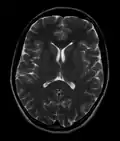

Brain regions on T1 MRI -

MRI image of the surface of the brain.